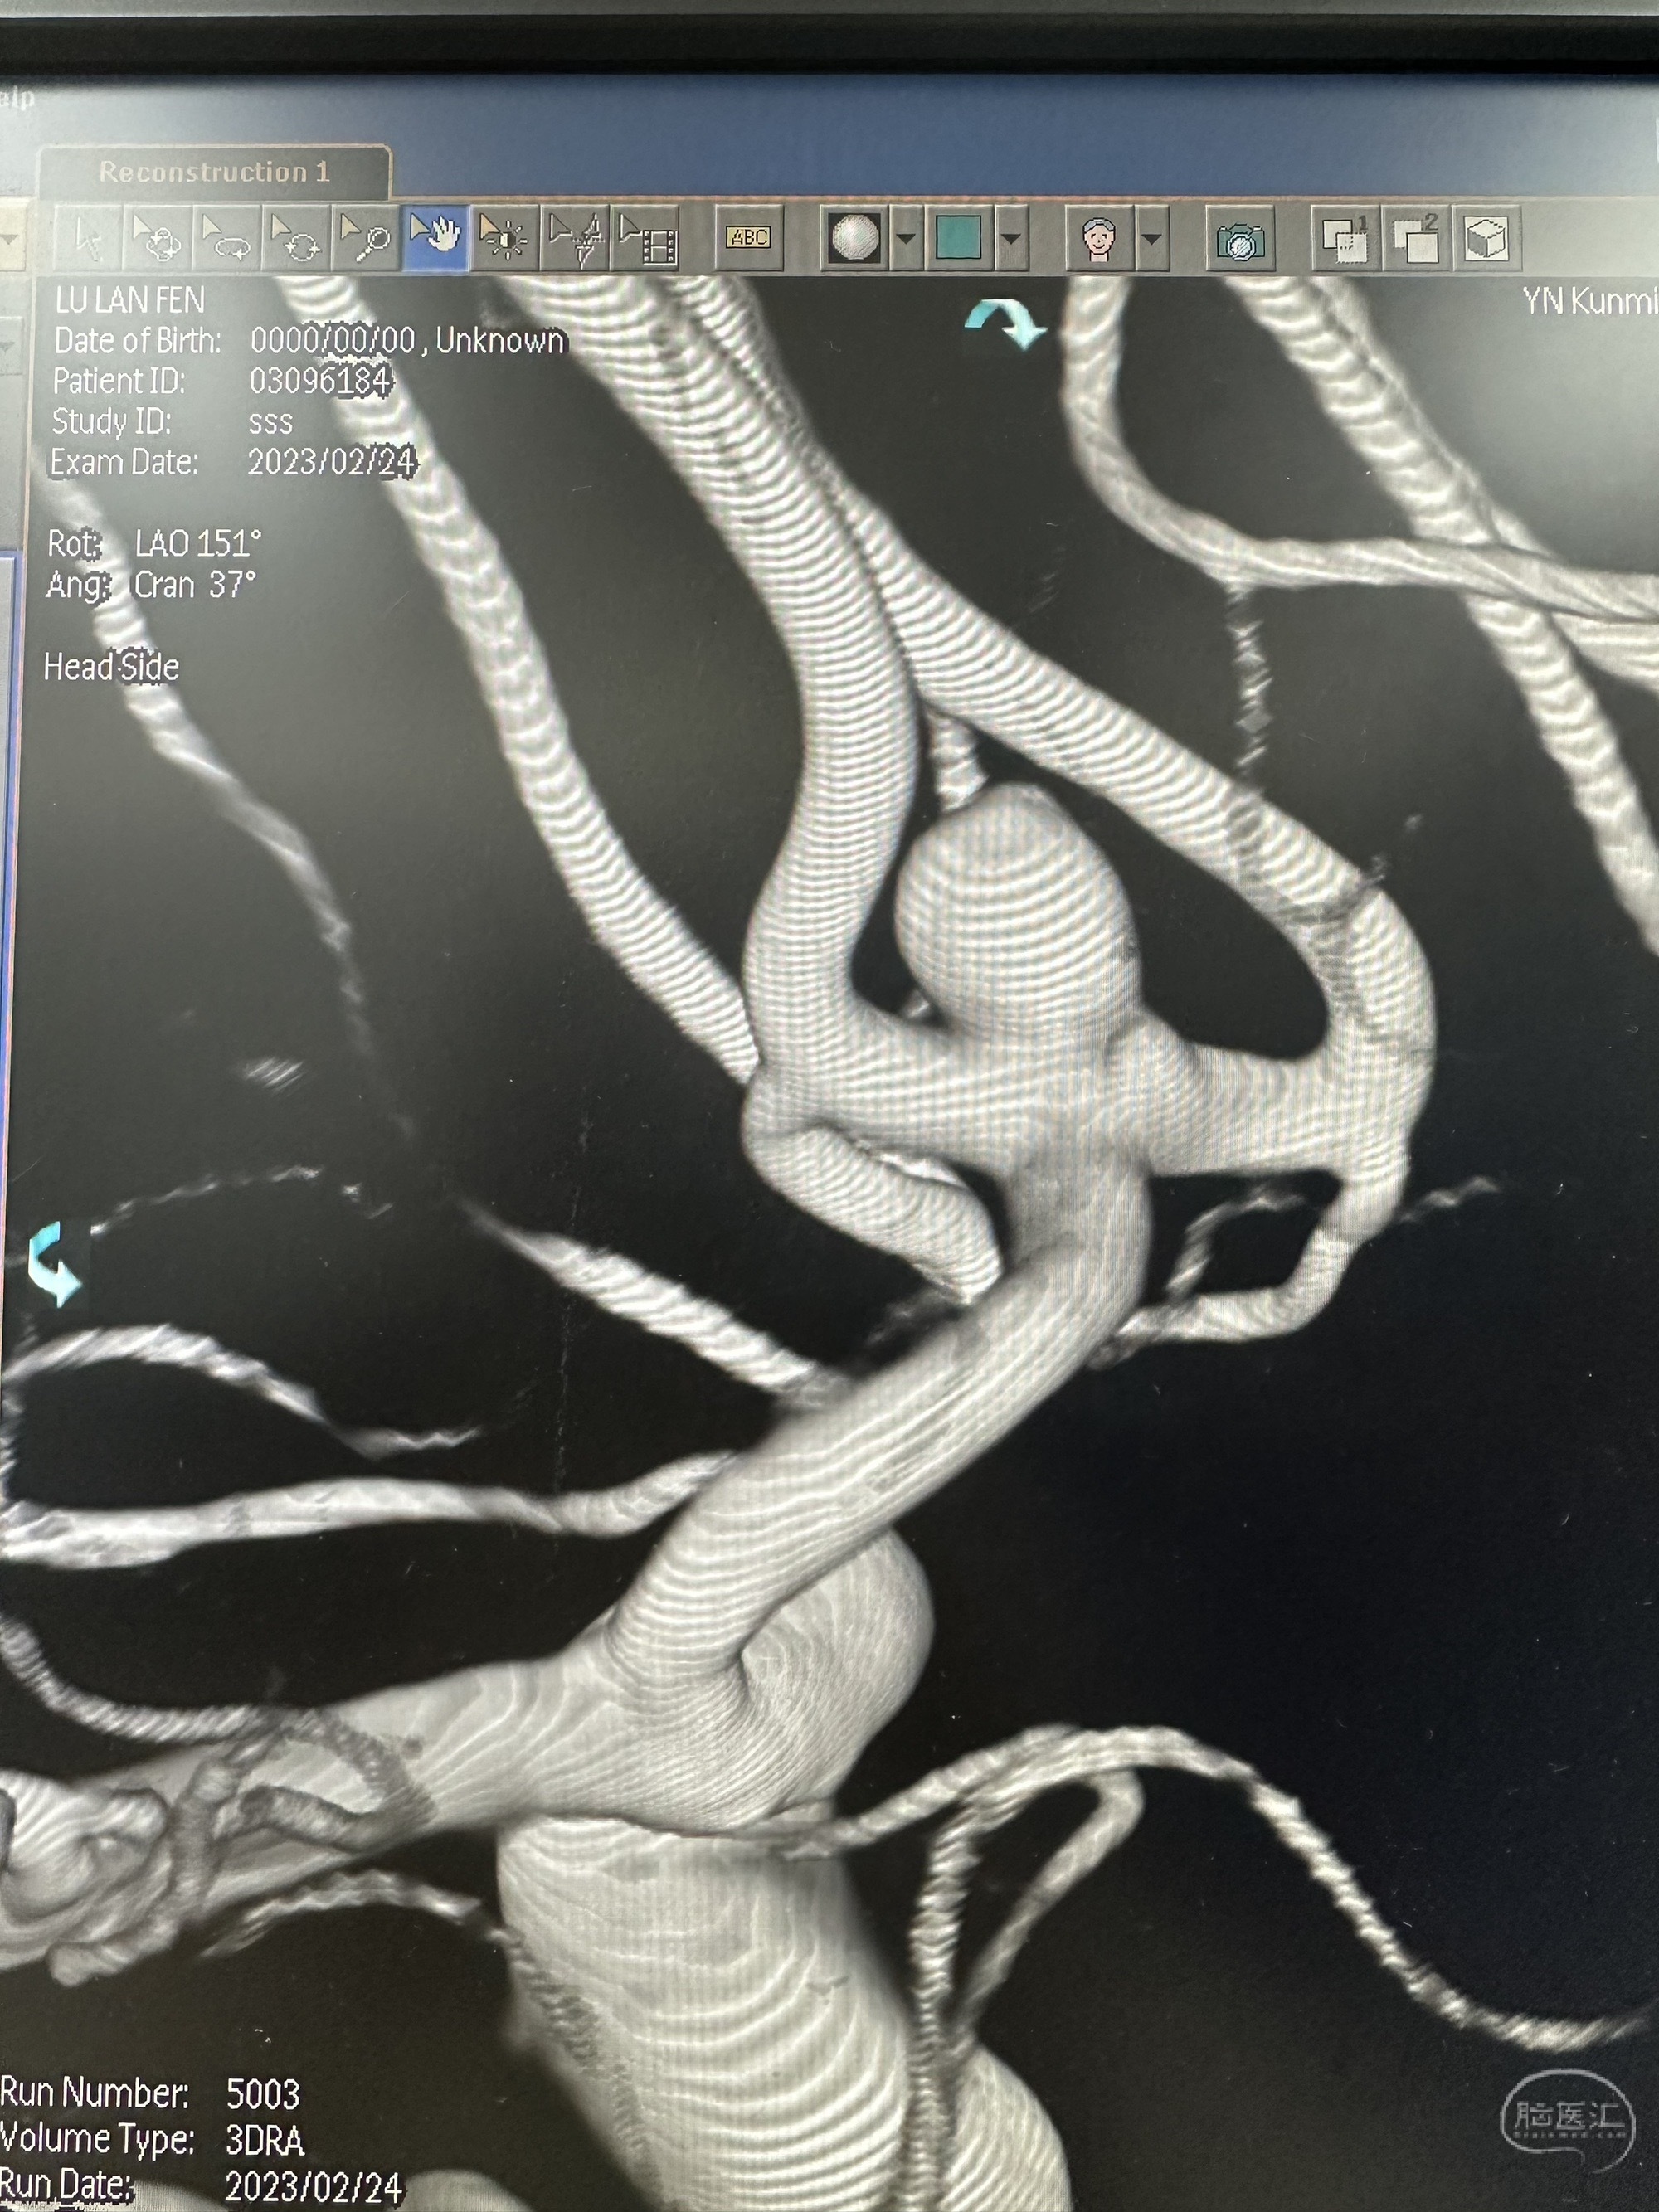

3D造影

另外一个角度